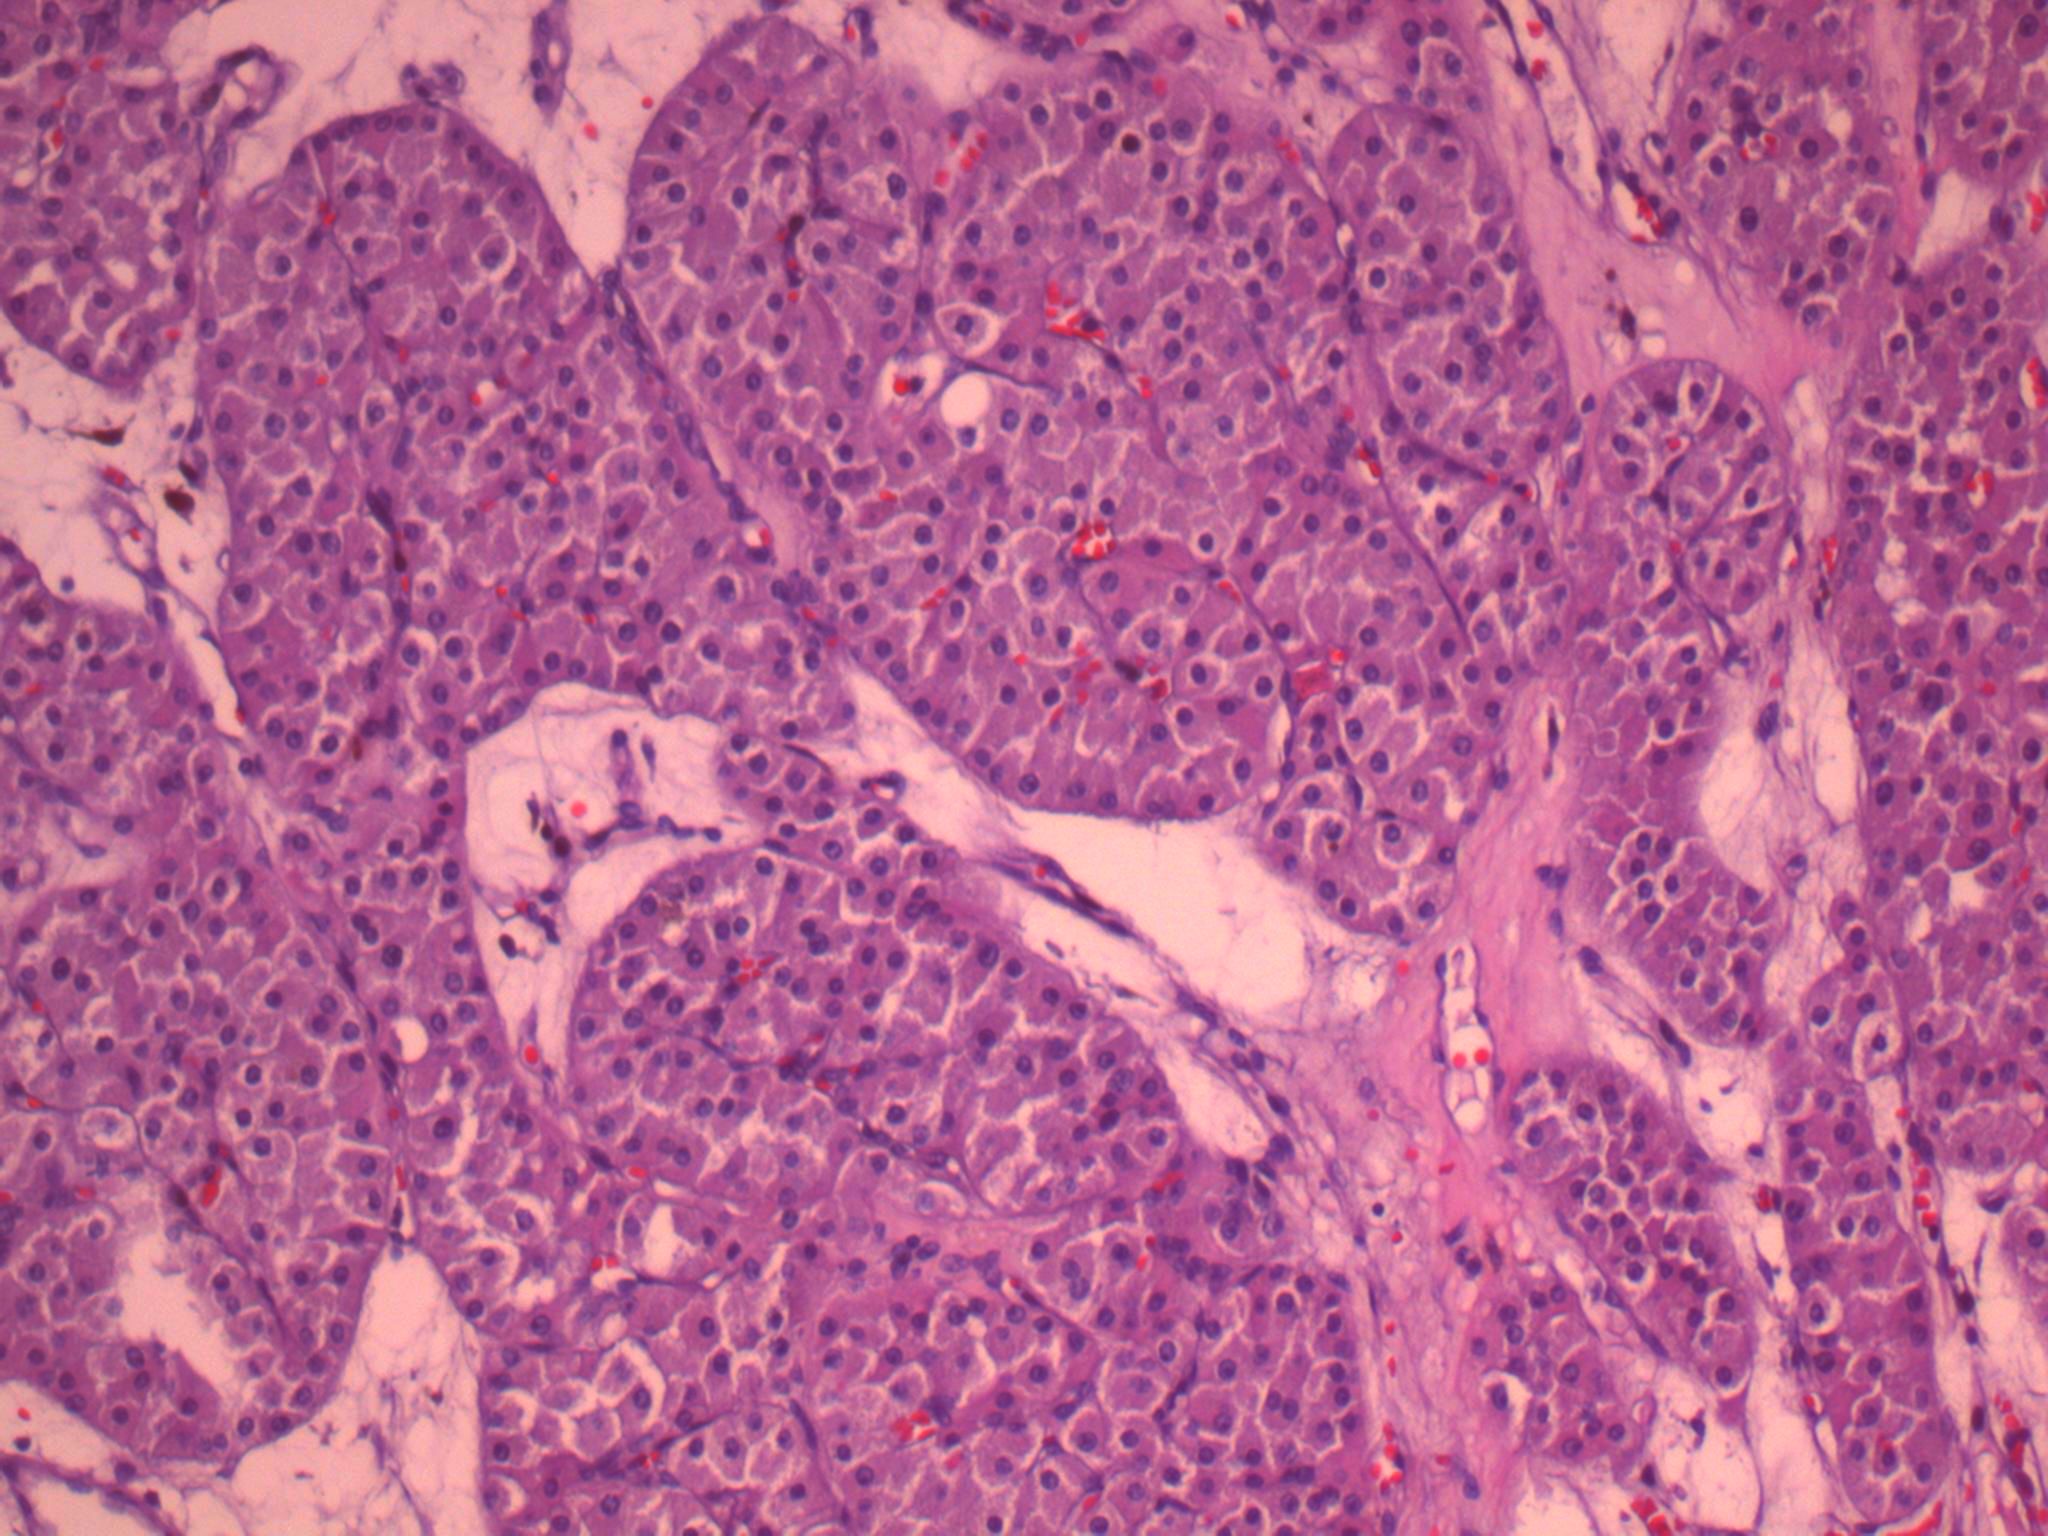

Case ID: 464

Consensus grade: I would not grade this tumor

Case description (by case creator):

Oncocytic neoplasm